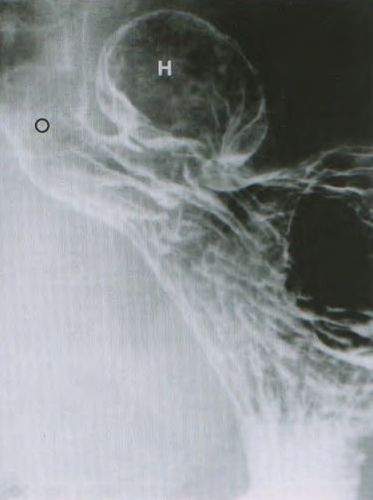

7.2. X quang thực quản - dạ dày cản quang [1]:

X quang thực quản - dạ dày cản quang là một trong số cận lâm sàng được chỉ định để chẩn đoán xác định thoát vị khe hoành, cung cấp thông tin về sự trải rộng của khối thoát vị, giúp phân biệt thoát vị trượt và thoát vị cuộn qua xác định vị trí của tâm vị.

Trên phim X quang thực quản - dạ dày cản quang bình thường, vòng B (khớp nối dạ dày - thực quản), có thể nằm bên trên ≤2 cm hoặc nằm bên dưới lỗ thực quản.

Trong thoát vị khe hoành, sự thoát vị có thể được nhận ra với sự hiện diện của nếp niêm mạc dạ dày bên trong túi thoát vị. Thực quản bị xoắn có thể có một khớp nối lệch tâm với khối thoát vị.

Tiêu chuẩn thoát vị khe hoành loại I: khe hoành rộng hơn 3 cm, có ít nhất 5 nếp niêm mạc chạy xuyên qua khe hoành, khớp nối dạ dày thực quản di chuyển lên cao hơn 2 cm bên trên khe hoành (bình thường khớp nối dạ dày - thực quản chỉ ≤ 2cm).

H: khe hoành

S: dạ dày nằm bên trên khe hoành

B: vòng B (khớp nối dạ dày - thực quản)

V: thực quản

Nguồn : A.H.A. Chapman, (2000)